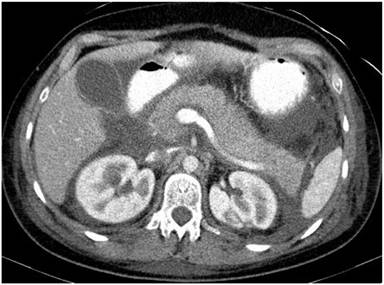

A 31-year-old female with past history of miscarriage (gravida 2, para 0) was admitted to a district general hospital at the 33rd gestational week complaining of upper abdominal pain and nausea. At the time of admission her vital signs were stable. Gynecological examination showed no evidence of premature labor: uterus tone was normal and cervix was closed. Her WBC were 15,000 mm-3 (reference range: 4,000-9,000 mm-3), CRP 65 mg/L (reference range: 0-5 mg/L). On the second day the symptoms of peritonitis developed; acute appendicitis was suspected and the patient underwent emergency laparotomy. Chylous ascites was drained; however, no cause of peritonitis was found intraoperatively. A normal appendix was removed. Post-operative blood tests were non evaluable due to high lipemia. On the third day of admission, she was transferred to a tertiary university hospital, where blood analysis showed increased level of triglyceride 87.5 mmol/L (reference range: 0-1.8 mmol/L), CRP 418 mg/L (reference range: 0-5 mg/L), procalcitonin 1.19 µg/L (reference range: 0-0.05 µg/L), lactate 5.78 mmol/L (reference range: 0.63-2.44 mmol/L), lipase activity 1,176 IU/L (reference range: 8-78 IU/L), and WBC 13,470 mm-3 (reference range: 4,000-9,000 mm-3), neutrophils 92% (reference range: 50-72%). The hematocrit was 36.2% (reference range: 36-42%). Electrophoretic pattern of lipoprotein was consistent with type V hyperlipoproteinemia. High concentrations of amylase (3,520 IU/L) and lipase (39,160 IU/L) were found in drainage fluid. Abdominal US revealed hypoechoic structure and blurred edge of the pancreas. Due to impending signs of fetal hypoxia an emergency Caesarean section was performed on the fourth day of hospitalization and healthy newborn female was delivered. Exploratory laparotomy revealed fat necrosis in the peripancreatic retroperitoneal space, omentum, and mesenteric root. Abdominal CT confirmed the diagnosis of acute pancreatitis (Figure 1). After delivery, triglyceride remained high (43.76 mmol/L) despite conservative hypertriglyceridemia treatment with heparin and insulin. Three sessions of plasmapheresis were performed with the aim of reducing hypertriglyceridemia. She was discharged at the 30th hospitalization day with triglyceride concentration of 4.75 mmol/L and cholesterol of 6.07 mmol/L (reference range: 0-5.2 mmol/L).

Figure 1. CT image shows a diffusely enhancing and enlarged pancreas with hypodense foci in the pancreatic head; increased density of the peripancreatic tissue and a large amount of fluid in abdominal cavity. |